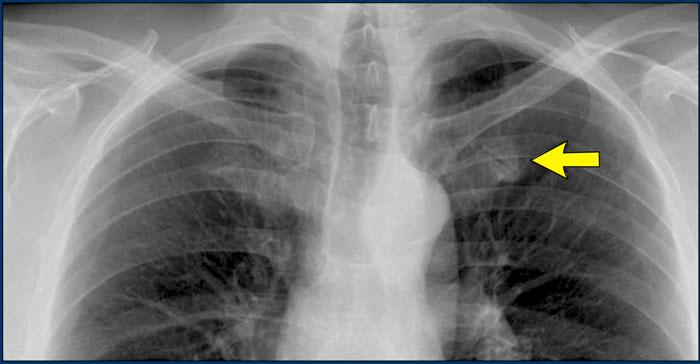

Ca lâm sàng 1: Tư thế PA

- Bờ tim trái bị xóa mờ trên phim X-quang tư thế PA.

- Ngay cả khi chưa xem phim nghiêng, dấu hiệu này đã định khu tổn thương ở phân thùy trước của phổi trái, nhiều khả năng là thùy lưỡi.

- Chẩn đoán: Viêm phổi thùy do Streptococcus pneumoniae.

Ca lâm sàng 2: Tư thế PA

- Quan sát thấy đám đông đặc ở thùy dưới trái (mũi tên vàng).

- Bờ tim trái vẫn được xác định rõ với bóng silhouette bình thường (mũi tên xanh dương), cho thấy tổn thương nằm ở phía sau và không liên quan đến thùy lưỡi.